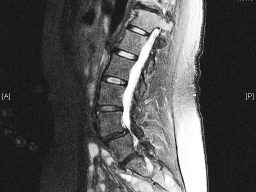

After clinical examination a X ray was done in bending position , Flexion and extension x ray which shows a slip of L4 bone over L5 bone resulting in nerve compression. MRI of spine is

advised to arrive at diagnosis

Spinal stenosis with spondylolisthesis (slip of one bone over another resulting in nerve compression) at L4-5 diagnosed as the cause of leg pain AND difficulty in walking with heaviness

and numbness in legs .

L4-5 Lumbar Spinal Stenosis nerve compression due to spondylolisthesis (slip of one bone over another ) with Lumbar Canal stenosis

Tubular Micro endoscopic spine surgery (decompression and spinal fusion) MIS TLIF was done with small incision in spine using tubular retractor and microscope by Dr. Vishal Kundnani at spine clinic Mumbai. Spinal Stenosis with spondylolisthesis surgery done with Minimal invasive spine surgery with transforaminal interbody fusion (MIS TLIF) technique by Dr. Vishal Kundnani using small incision of 2 cm only . Patient got immediate relief and no bed rest required with early return to work.